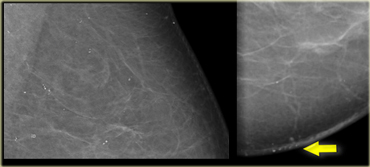

High grade DCIS High grade DCIS

On the left fine linear and branching calcifications in a segmental distribution highly suggestive of malignancy (Bi-RADS 4C).

Extensive high grade DCIS was found at biopsy.